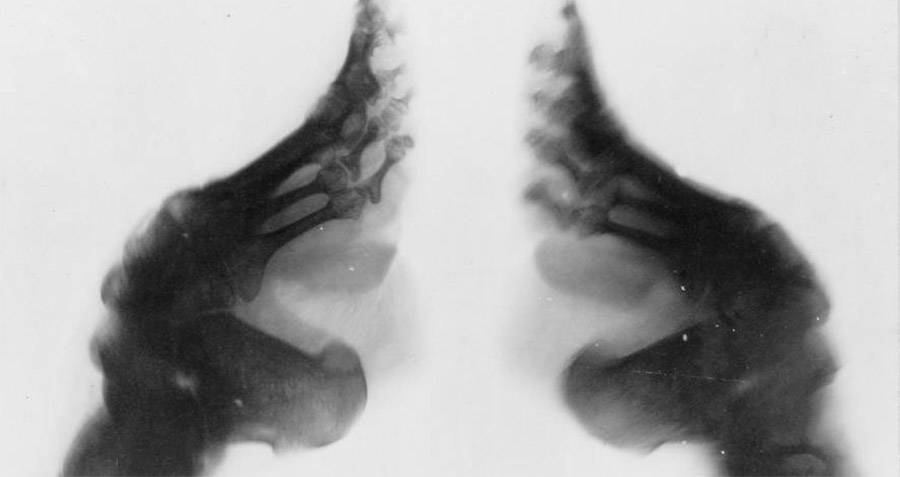

Wikimedia CommonsAn X - light beam of bound feet .

Wikimedia CommonsAn X-ray of bound feet.